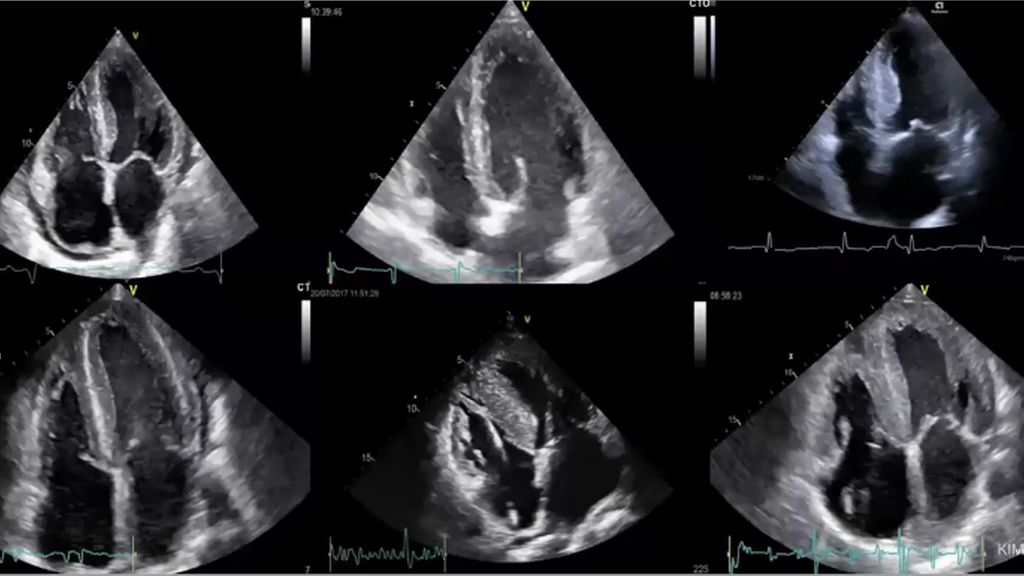

Nach dem Studium des Videolearnings haben Sie einen Überblick über die Diagnostik seltener hypertropher Kardiomyopathien. Dabei wird ein besonderer Fokus auf die Diagnostik mittels EKG gelegt. Beispiele helfen dabei, hypertrophe Kardiomyopathien künftig besser zu erkennen.